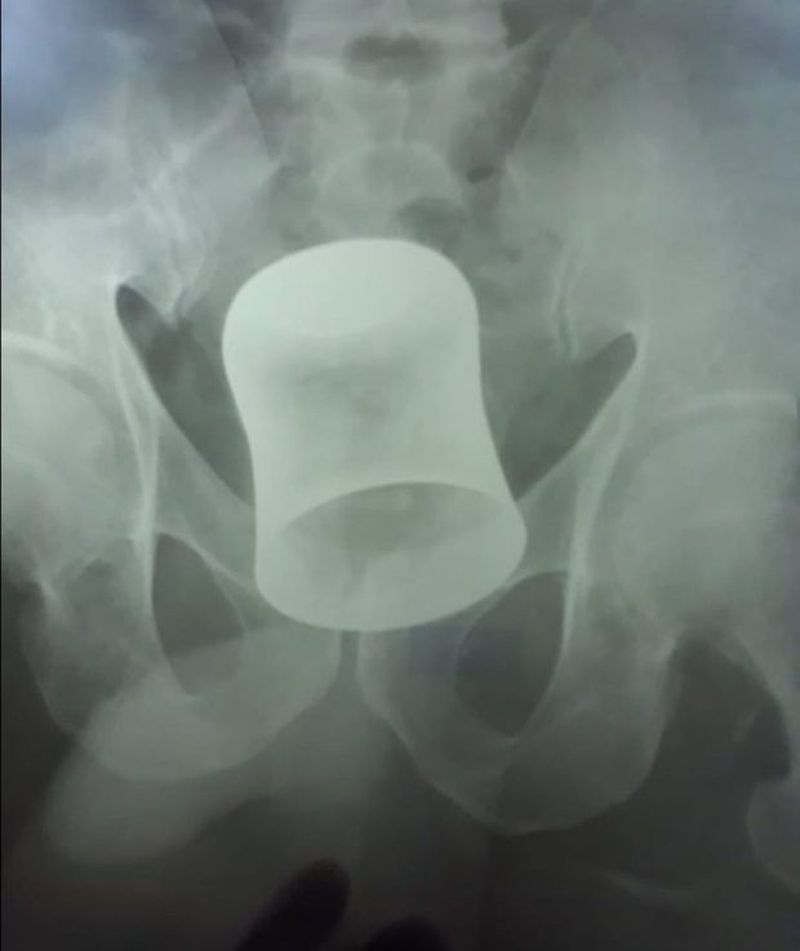

Zece zile mai tarziu a venit la spital, iar radiografia a aratat ca avea in el o cana din metal in anus. Medicii l-au operat de urgenta.